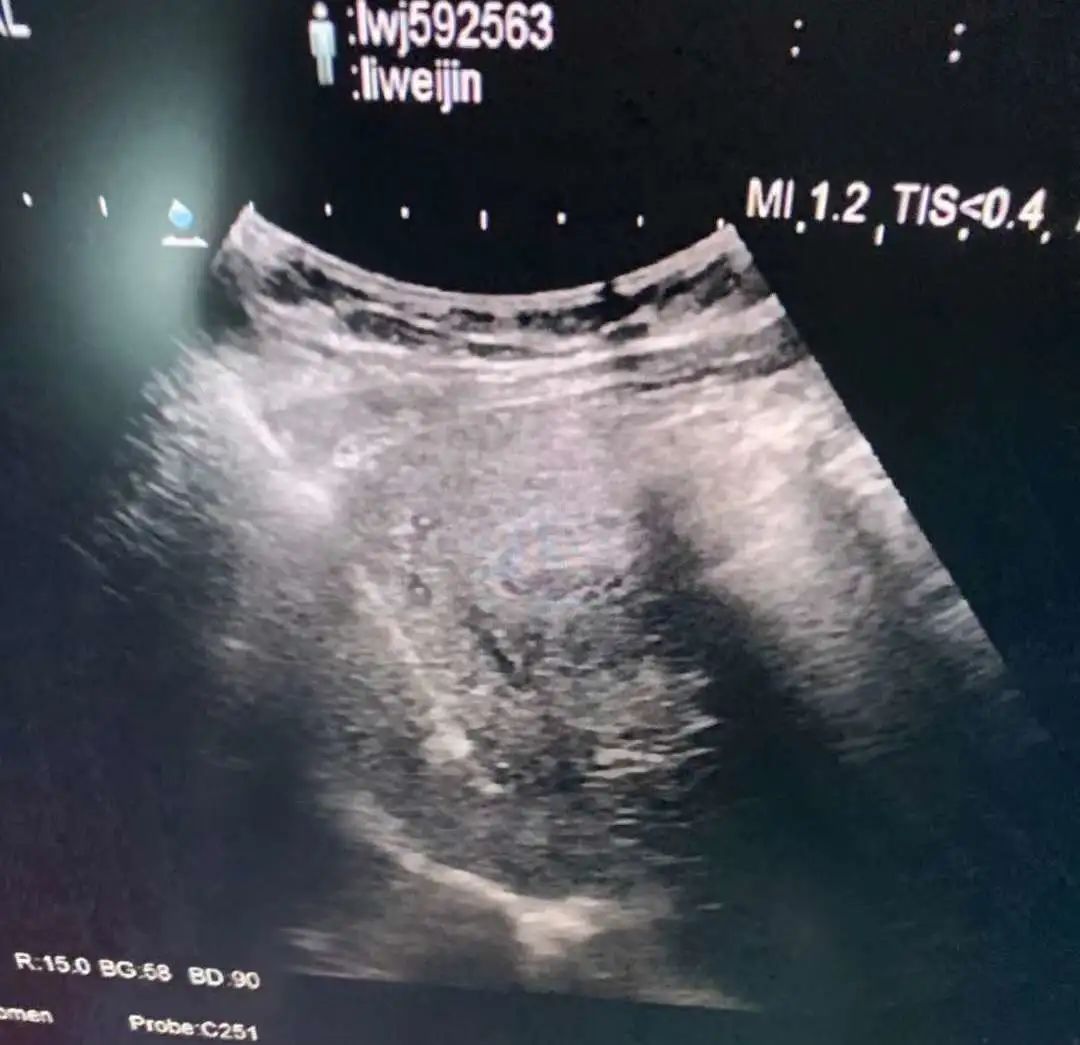

超声引导下肿瘤消融治疗是在实时超声的监视引导下应用专门的治疗针,达到不开刀、对体内的肿瘤原位灭活的一门新技术,其中肝癌经皮微波凝固治疗处国际领先地位。

微波消融治疗肝癌可采用经皮穿刺、开腹手术术中消融或经腹腔镜引导几种方式,超声引导下准确地摆放微波辐射电极,保证凝固坏死区完全覆盖整个肿瘤,达到完全灭活肿瘤。对于小于3厘米的肝癌,射频、微波消融治疗技术成熟,已经取得和手术相同的临床效果,但微创、安全、经济、痛苦小是手术方法无法替代的,尤其是无法耐受手术及复发和转移的肝癌。